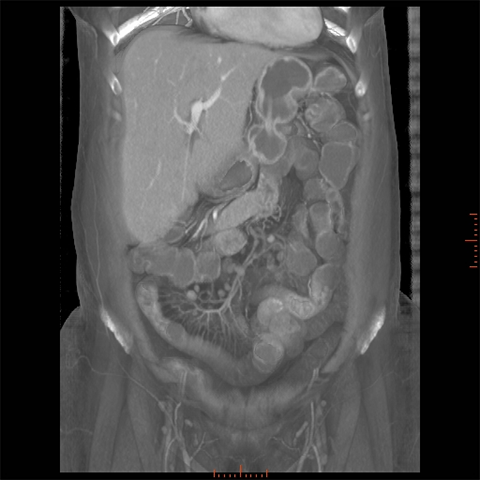

56 year-old male with Crohns Disease presents with persistent abdominal pain and diarrhea. [1 of 4]